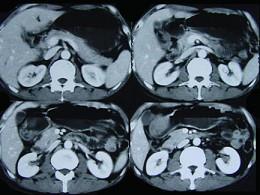

问题 女性,42岁,腹痛、黑便1周,CT扫描见胃窦部圆形块影,最佳的诊断是()

选项 A.胃窦平滑肌瘤 B.胃癌 C.胃淋巴瘤 D.胃窦神经纤维瘤 E.胃内异物

答案 D